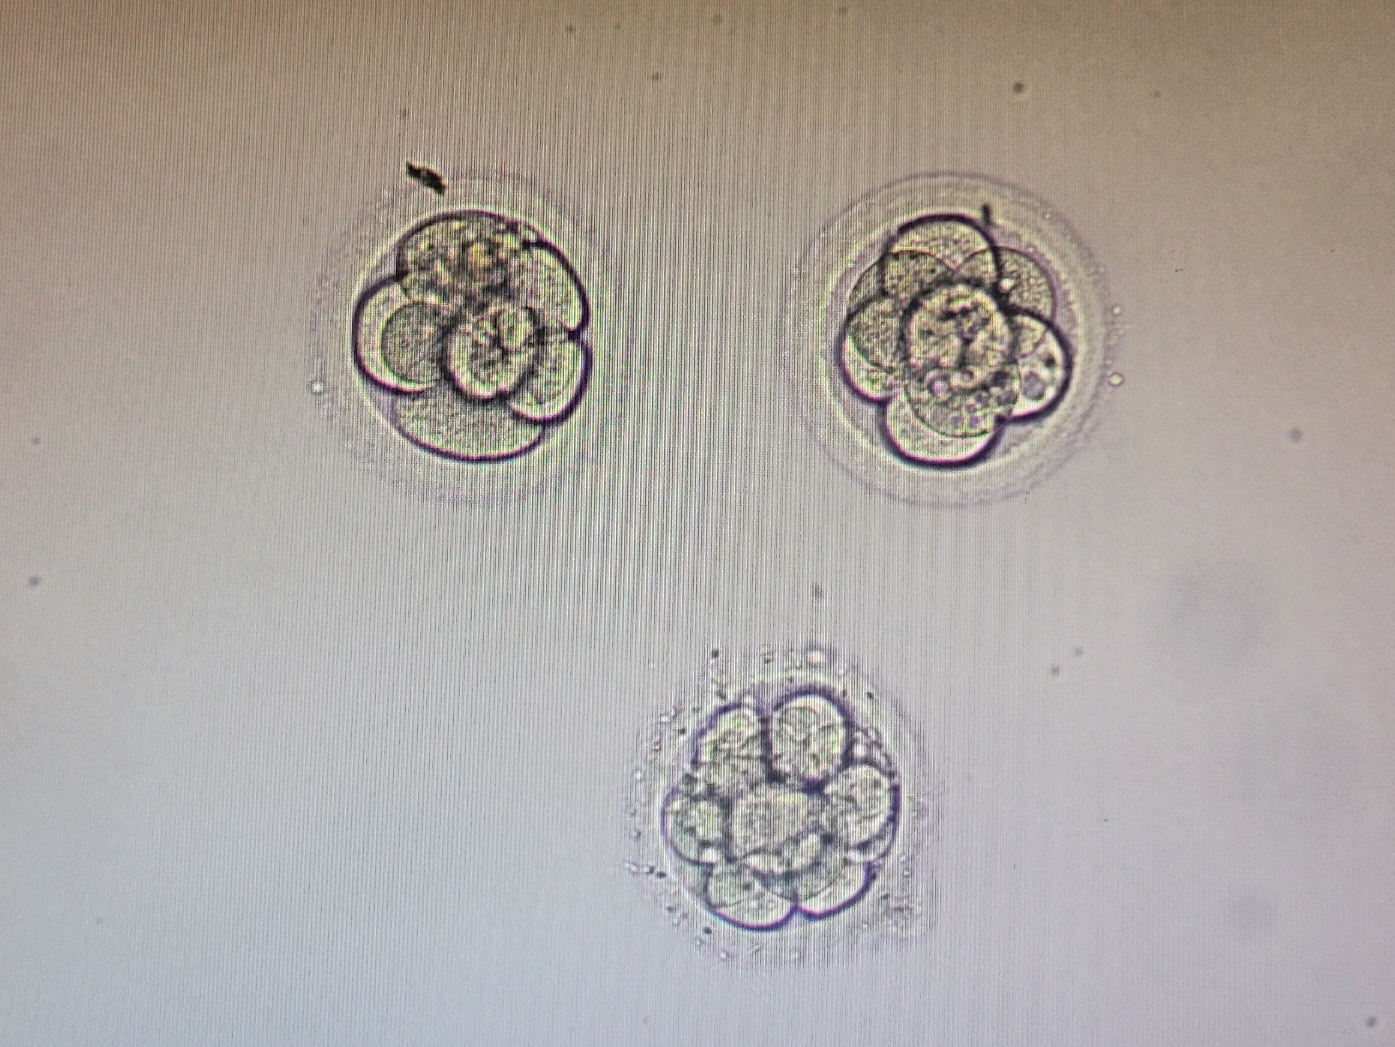

시험관 1차를 진행하면서 특별히 불편했던 부분이 없었기 때문에, 2차도 '미래와 희망'에서 진행 예정이다. 시험관 시술 단계별로 구체적인 내용은 2차 과정을 기록하면서 최대한 남겨보겠다. 아마 병원마다 처방하는 주사나 약은 다르겠지만 과정은 비슷할 것이고, 아이를 기다리는 예비엄마들의 마음은 다 같지 않을까 싶다. 막연하게 느껴지는 길을 함께 걸어가는 사람이 있다는 사실이 당신에게 작은 위안이라도 되었으면 좋겠다. 지난 1월, 내 마음에 꽃처럼 피었다가 사라진 배아 사진을 오랜만에 꺼내보니 기분이 참 묘하다. 이번에는 우리 가족의 곁에 오래 머물러 주었으면 하는 바람이다. 10개월의 기다림 끝에 너를 꼭 만나고 싶다.